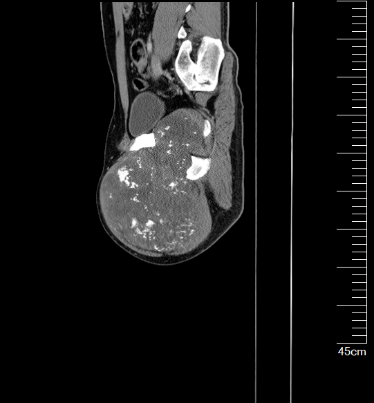

图片 4.png图片 5.png图片 6.png

术前MR